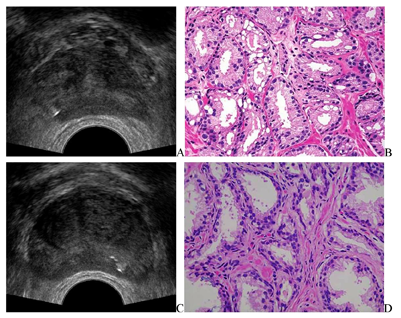

(2)前列腺穿刺活检(图2):采用经直肠引导下经会阴穿刺活检术,穿刺方案为目标穿刺联合12点系统穿刺,共穿刺15针。穿刺病理诊断:右侧周缘区外侧、右侧周缘区中部、右侧周缘区旁正中为前列腺腺癌,Gleason评分3+3。